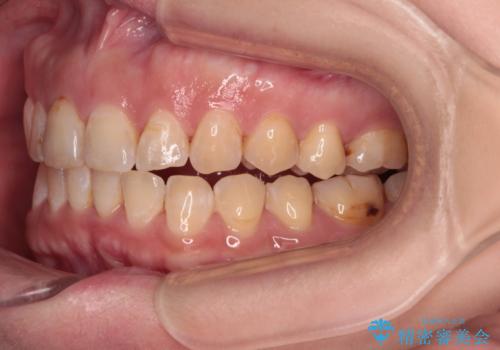

- 飛び出た上の前歯を気にして来院された患者様です。

奥歯の咬み合わせは、上顎歯列が理想的な一よりも数mm前方にある状態でした。

なるべく早めに治療を終えたいとのことで、補助装置を用いて上顎臼歯を後方に移動させ、同時にワイヤー装置にて整えることとしました。

舌の突出癖が原因で上下の歯に大きなスペースが生じていたため、舌のトレーニングをしっかり行っていただくことで、上顎歯列をスムーズに移動させることができました。